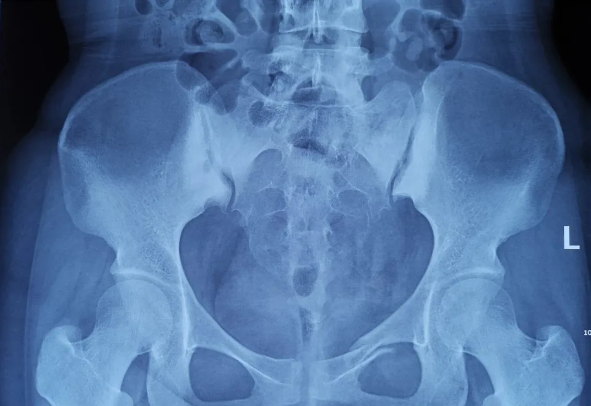

患者为22岁年轻女性,因车祸致骨盆骨折。骨盆骨折是一种复杂的创伤,传统手术方式需要比较大的切口,而且骨盆内有大量复杂血管和神经,手术难度和风险极大,是很多骨科医生的禁区。

在传统骨科手术中,反复使用X线透视,有时须经常调整或更改手术固定方式,常常需要多年的临床经验积累,也难免意外频发,毕竟人眼判断和X线透视单平面观察的局限性是客观原因。